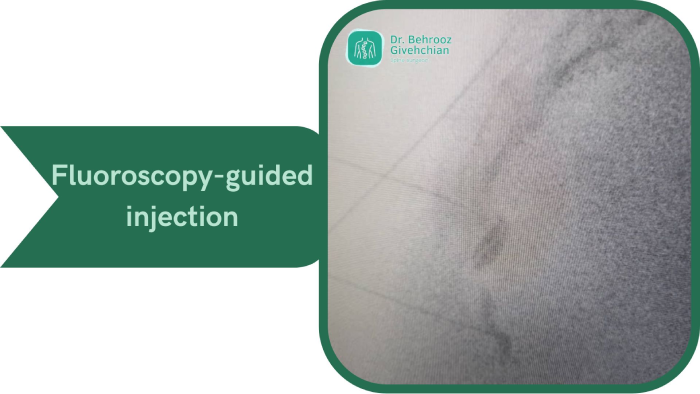

۲. تزریق موضعی

تزریق موضعی داروهای ضد التهاب مانند کورتون میتواند تأثیر قابلتوجهی داشته باشد. این تزریق معمولا تحت هدایت سونوگرافی یا فلوروسکوپی (اشعه ایکس زنده) انجام میشود تا دارو دقیقاً در محل التهاب و اطراف مفصل دنبالچه تزریق شود.